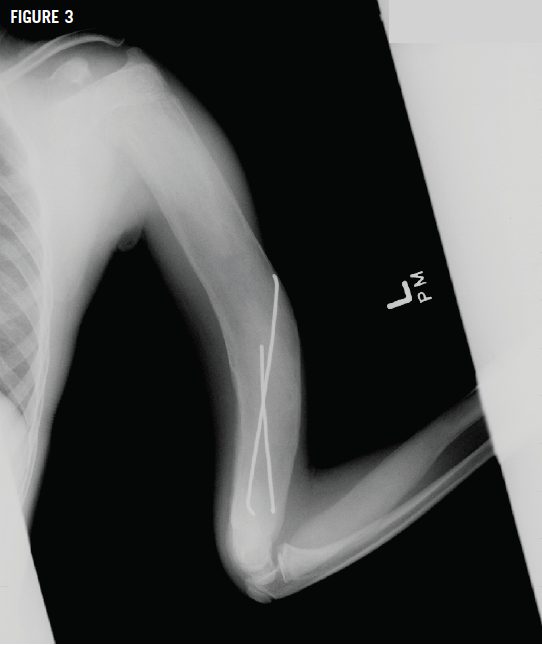

Radiographs of the left humerus showed lesions with ground-glass opacity and a Madelung deformity of the wrist (Figures 3 and 4), suggesting polyostotic fibrous dysplasia (FD). Bone age and chronologic age were similar. Results of magnetic resonance imaging of the brain were normal.